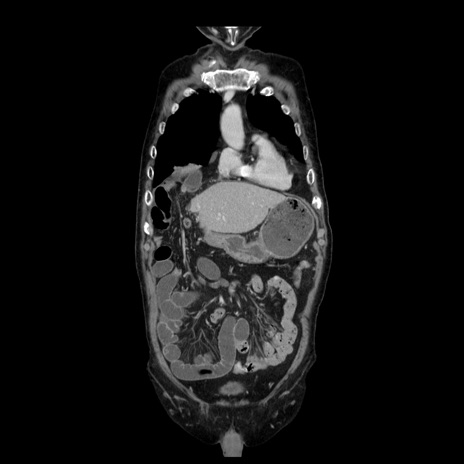

症例21(冠状断像)

【症例】70歳代男性

【主訴】腹痛

【現病歴】肝硬変・肝細胞癌にてかかりつけの方。約9時間前に食後より腹痛出現。症状が徐々に増悪し、嘔吐出現したため来院。

【既往歴】肝硬変、肝細胞癌(RFA、TACE後)

【身体所見】意識清明、表情苦悶様、BT 36℃、BP 129/78mmHg、P 88bpm、SpO2 97%(RA)、右上腹部から心窩部にかけて圧痛あり、反跳痛なし、筋性防御あり。

【データ】WBC 5800、CRP 0.16